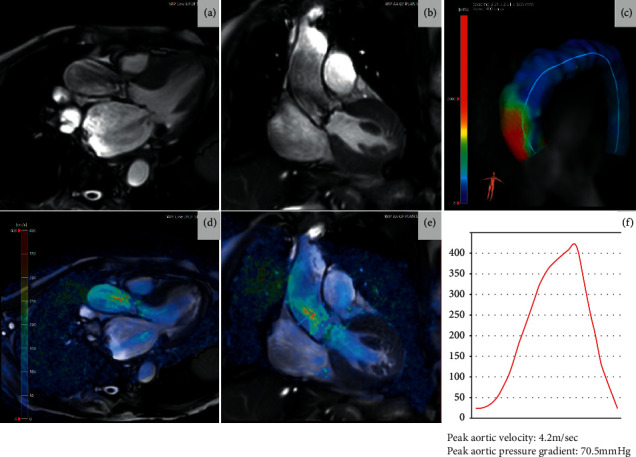

心血管磁共振成像(CMR)对了解各种疾病的过程和病理生理机制产生了巨大影响。最近,它对瓣膜性心脏病患者的诊断和风险分层做出了重大贡献。随着 CMR 的应用越来越广泛,它可以对左心室容积和质量进行详细、可重复、定性和定量的评估,从而评估瓣膜病变对心肌的血流动力学影响。利用特征跟踪 CMR 方法对常规获取的图像进行后处理,可获得有关心肌变形和应变参数的宝贵信息,这些信息表明存在亚临床心室损伤,而射血分数(EF)等传统测量方法仍无法检测到这些损伤。由于越来越多的证据表明纤维化的存在与不良事件和预后有关,因此 T1 图谱和晚期钆增强 (LGE) 成像可提供深层心肌组织特征,从而改变了对患者进行风险分层的方法。本综述总结了目前有关 CMR 在主动脉瓣狭窄或二尖瓣反流患者左心室评估中的作用及其在诊断、风险分层和管理中的价值的证据。

Cardiovascular magnetic resonance (CMR) imaging has had a vast impact on the understanding of a wide range of disease processes and pathophysiological mechanisms. More recently, it has contributed significantly to the diagnosis and risk stratification of patients with valvular heart disease. With its increasing use, CMR allows for a detailed, reproducible, qualitative, and quantitative evaluation of left ventricular volumes and mass, thereby enabling assessment of the haemodynamic impact of a valvular lesion upon the myocardium. Postprocessing of the routinely acquired images with feature tracking CMR methodology can give invaluable information about myocardial deformation and strain parameters that suggest subclinical ventricular impairment that remains undetected by conventional measures such as the ejection fraction (EF). T1 mapping and late gadolinium enhancement (LGE) imaging provide deep myocardial tissue characterisation that is changing the approach towards risk stratification of patients as an increasing body of evidence suggests that the presence of fibrosis is related to adverse events and prognosis. This review summarises the current evidence regarding the utility of CMR in the left ventricular assessment of patients with aortic stenosis or mitral regurgitation and its value in diagnosis, risk stratification, and management.